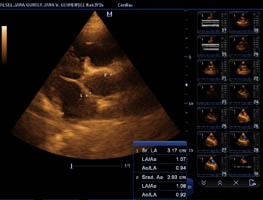

Gesundheitsstatus vom 26.11.2018 Die Röntgenbilder zeigen keinen Hinweis auf HD oder ED bei Lena vom Gehrensee. Die veterinärmedizinischen Untersuchungen von Jana auf HD, ED u. DCM und die Zuchtzulassungsprüfung wurden erfolgreich bestanden.

Die Gelenke sind HD und ED - frei, das Herz ohne Befund. Vor dem Hintergrund, dass seit 5 Generationen alle Zuchthündinnen bis ins hohe

Alter eine hervorragende Herzleistung hatten und bei ihnen niemals Herzprobleme auftraten, sind solche aufwendigen Ultraschalluntersuchungen

eine reine Routinesache. Hinzu kommt, dass die Mutterhündin (im Ruhestand) "Indra" mit 6 Jahren durch eine extrem hohe Fitness in Bezug

Herzultraschall von Lena vom Gehrensee zur Vermeidung von DCM

Durch Klick auf die Übersicht können die Herzdaten eingesehen werden.

Der Herzcheck ergab keinen Hinweis auf DCM.